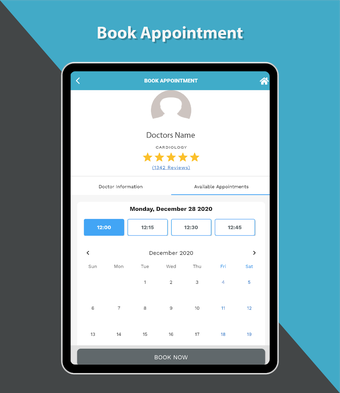

これは、Dr. Sulaiman Al-Habib Medical Services Groupが提供するすべてのサービスにアクセスするのを助ける無料のアプリです。グループの持続的なデジタル変革の重要な部分であり、効率と生産性の向上を重視しています。この新しいアプリは、オンライン医師相談から医療検査や放射線学の報告書まで、グループが提供するすべてのサービスに簡単にアクセスできるようになります。また、あなたと家族の医療記録を閲覧する機会も提供しています。